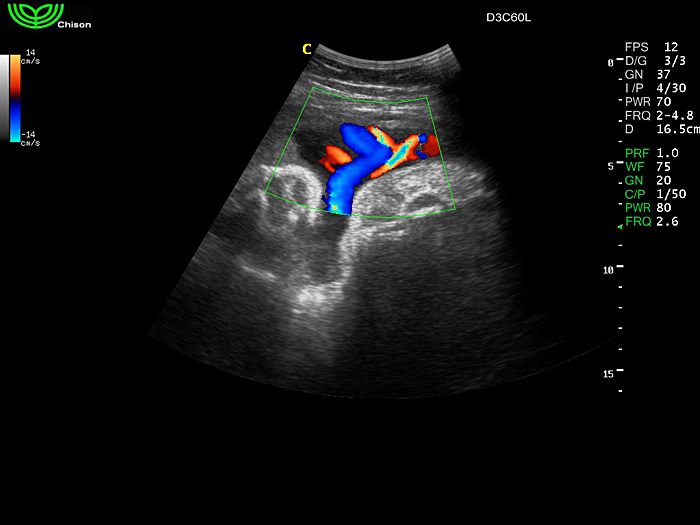

D3C60L 3.5МГц, конвексный.

2.0МГц - 5.8 МГц. Применения: абдомиальное обследование, акушерство, гинекология, обследование районной блокады нерва, осуществление и управление биопсией. |